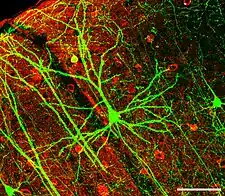

Neurology (from Greek: νεῦρον (neûron), "string, nerve" and the suffix -logia, "study of") is the branch of medicine dealing with the diagnosis and treatment of all categories of conditions and disease involving the nervous system, which comprises the brain, the spinal cord and the peripheral nerves.[1] Neurological practice relies heavily on the field of neuroscience, the scientific study of the nervous system.

Also, many nonmedical doctors, those with doctoral degrees (usually PhDs) in subjects such as biology and chemistry, study and research the nervous system. Working in laboratories in universities, hospitals, and private companies, these neuroscientists perform clinical and laboratory experiments and tests to learn more about the nervous system and find cures or new treatments for diseases and disorders.

A great deal of overlap occurs between neuroscience and neurology. Many neurologists work in academic training hospitals, where they conduct research as neuroscientists in addition to treating patients and teaching neurology to medical students.